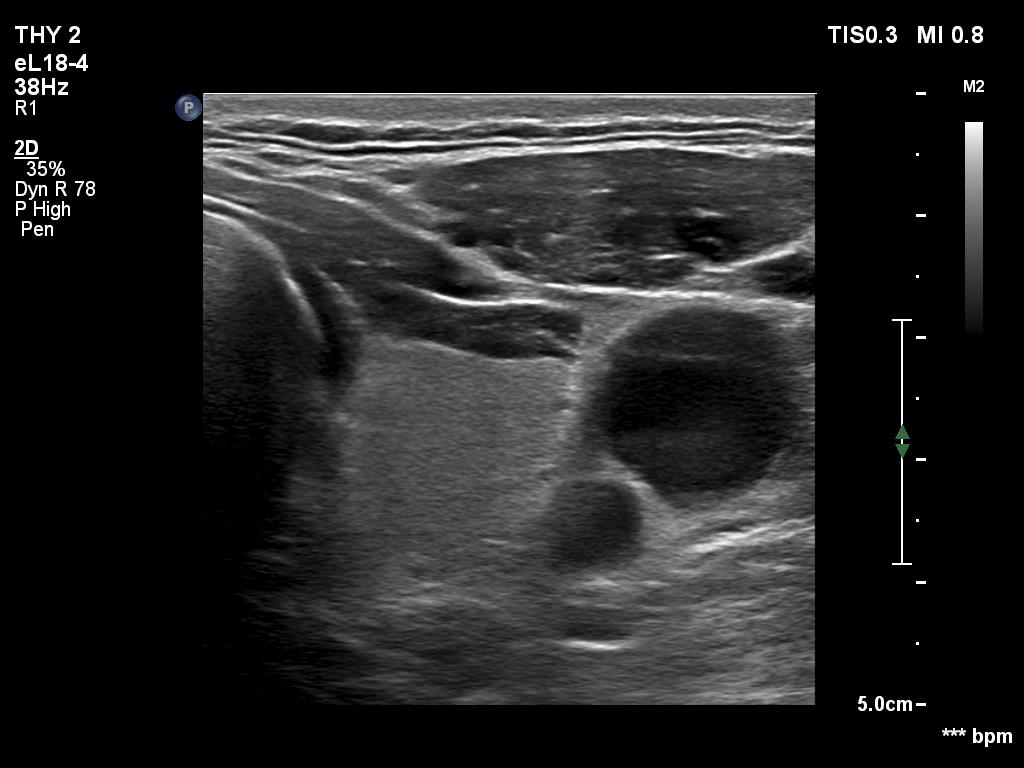

Ultrasonography. The thyroid was echonormal and had two cystic lesions in the left lobe. With higher frequency, the dorsal part of both lobes presented with hypoechoic blurred areas. With frequency decreased, these areas have disappeared.

Suggestion: ultrasound in five years.

Comment. This case illustrated the well-known inverse relation between penetrance and resolution. Better the former worst the latter and conversely. This has particular and practical importance if we examine obese patients using high-end equipment with high frequency. In such patients the obesity can significantly worsen the penetrance. This can be solved by decreasing the frequency and remove all software harmonization.